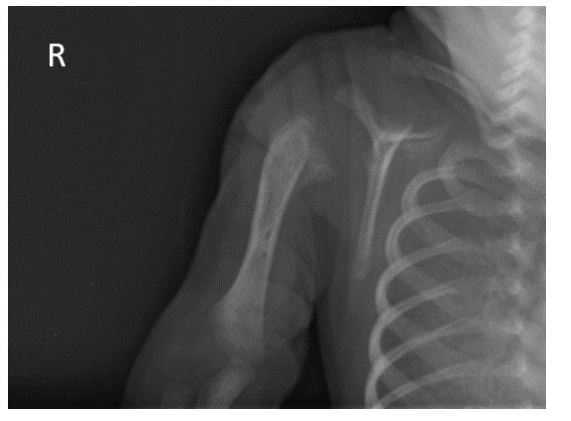

Subsequent radiograph confirmed slippage of the humeral epiphysis, as evidenced by hypertrophic callus formation at the proximal metaphysis (Figure 3).